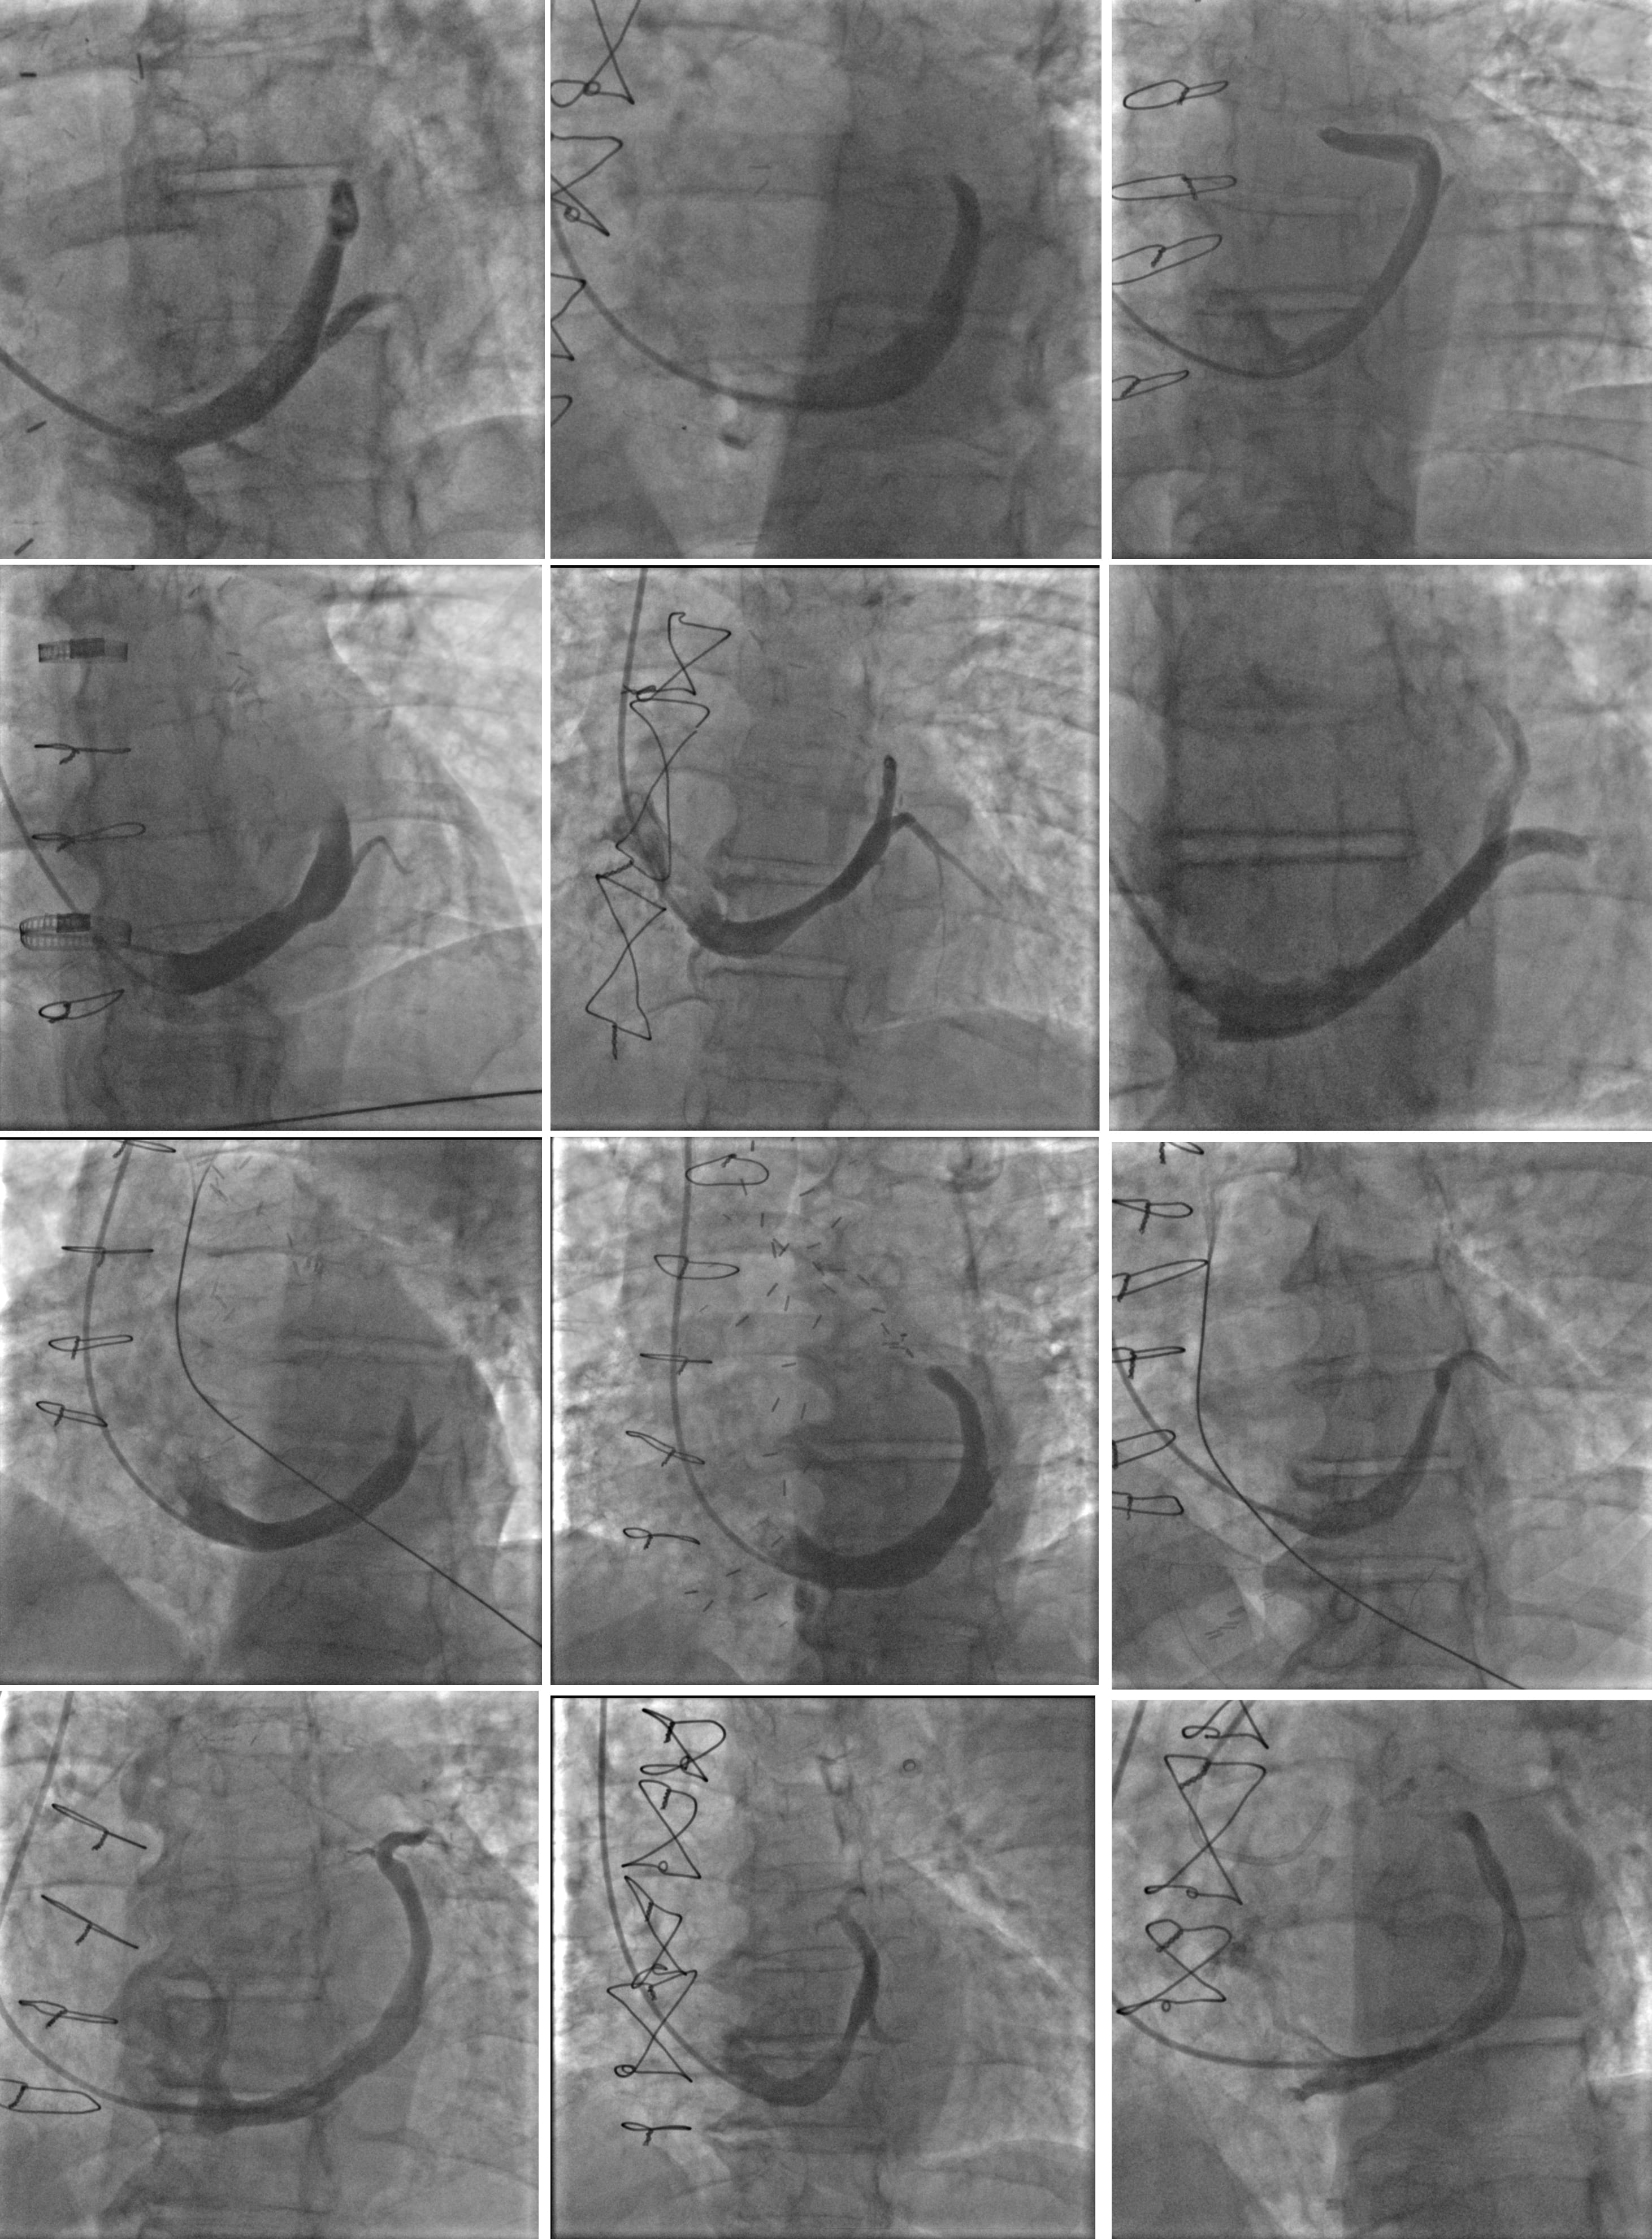

Most patients were male with extensive coronary artery disease. Altogether, 63% of patients underwent previous percutaneous, and 83% underwent previous surgical, revascularization. 83% of patients in the CSR group and 75% in the sham group had a non-revascularized chronic total occlusion (CTO) of at least one coronary artery. The extent of reversible ischemia was comparable between both groups and was primarily confined to the territory of the left coronary artery. All patients were receiving beta-blockers, and 92% of patients were receiving ranolazine. CSR implantation was successful in all patients randomized to the CSR group. Intraprocedural venograms of patients receiving CSR are presented in Fig. 2. Vein tributaries were delineated and allowed distal CSR implantation without visible lateral vein distal to the CSR narrowing. Inferior heart veins were drained to the distal end of the coronary sinus or separately to the right atrium.

Fig. 2.Coronary sinus venograms of 12 patients receiving coronary sinus reducer.